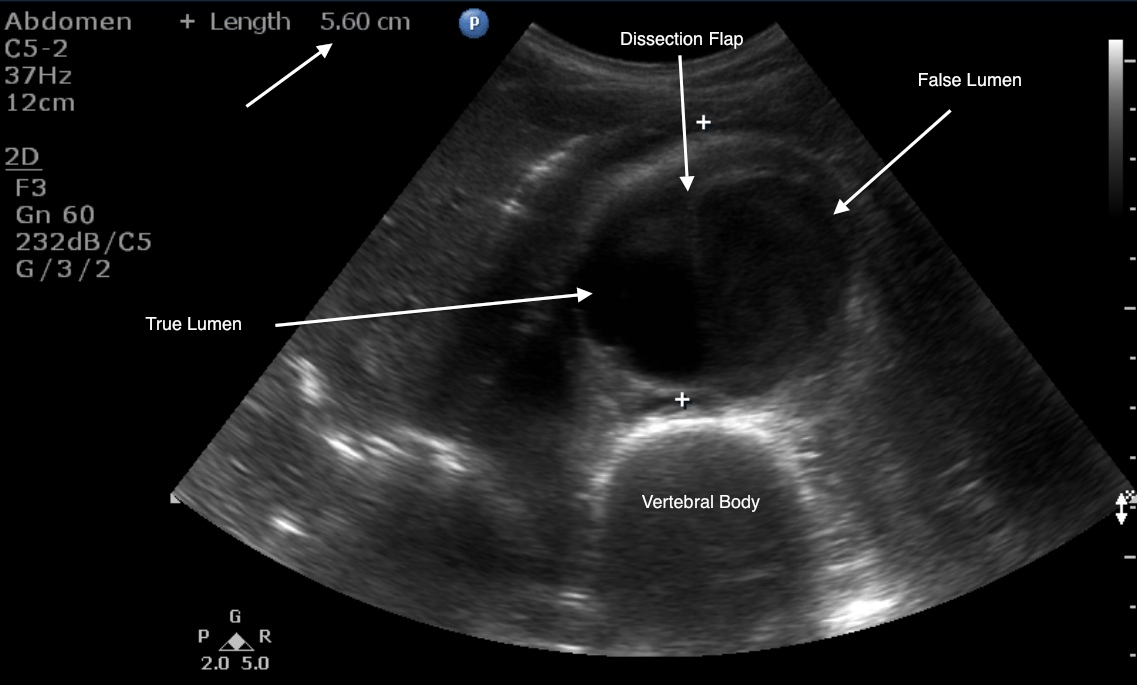

The IVC can be visualized in a transverse (short-axis) or in a sagittal (long-axis) orientation while scanning the abdomen. Imaging is performed with the patient in a supine position using the liver as an acoustic window. It is recommended to begin with a transverse view, with the probe indicator to the patient’s right side just below the xiphoid process. In this orientation, the vertebral body of the spine is seen as a bright hyperechoic structure with posterior shadowing. The aorta is seen in cross section just anterior to the spine as an anechoic blood-filled circular structure. The IVC is seen adjacent to the aorta on the patient’s right side as an anechoic circular or teardrop structure (see Chap. 5). The image on the screen will depict the IVC on the left side and the aorta on the right. As the IVC is followed toward the heart, the left, middle, and right hepatic veins will be seen to enter the IVC just before it enters the right atrium.

The IVC is located to the right of the abdominal aorta , and most of the IVC lies in the retroperitoneal space. Between the diaphragm and right atrium, the IVC has a very short intrathoracic segment ( Figure 18.1 ). From the subcostal cardiac window, the IVC appears as a large, intrahepatic vessel with thin walls, and under normal conditions typically demonstrates respirophasic variations in caliber ( Figure 18.2 and#N#Video 18.1#N#). The IVC is a capacitance vessel and thus is sensitive to changes in right atrial pressure and volume status. In spontaneously breathing patients, where the intrathoracic pressure becomes negative during inspiration, the normal response to inspiration is a decrease of IVC diameter ( Figure 18.3 ). In patients on positive-pressure ventilation, the respirophasic change of the IVC is reversed with inspiration causing IVC distention. IVC size may also be influenced by venous return from the splanchnic circulation, diaphragmatic excursions during breathing, and intra-abdominal pressure.

The inferior vena cava (IVC) is a large, thin-walled, retroperitoneal blood vessel formed by the confluence of the left and right common iliac veins. It carries the deoxygenated blood from the lower body and lower extremities to the right atrium. Before it drains into the right atrium, it runs a short course through the liver and collects blood from the hepatic veins. It also acts as a venous capacitance reservoir. The IVC typically runs on the right side of the spine. The image below shows it (the large blue vessel) lying next to the abdominal aorta (Figure 1). Rarely, there could be anatomical variants such as left-sided IVC and IVC duplication.

It also acts as a venous capacitance reservoir. The IVC typically runs on the right side of the spine.